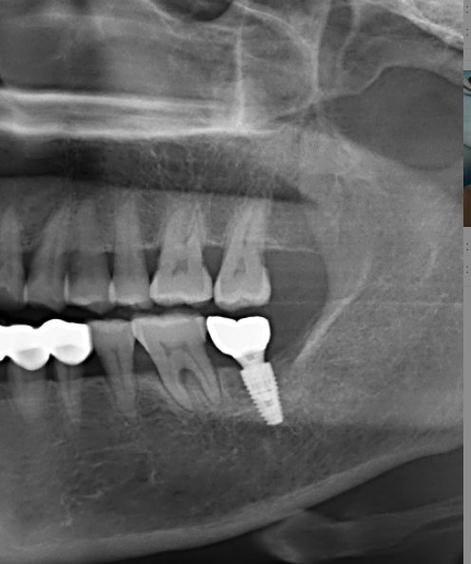

(图片来源网络,侵删)- 是否有《医疗机构执业许可证》,诊疗科目包含“口腔种植”。

- 是否配备CBCT(锥形束CT):这是种植前必须的检查,用于评估骨量、神经血管位置,是精准种植的基础。